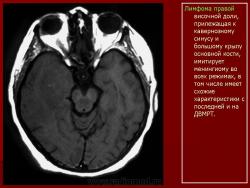

Лимфомы головного мозга.